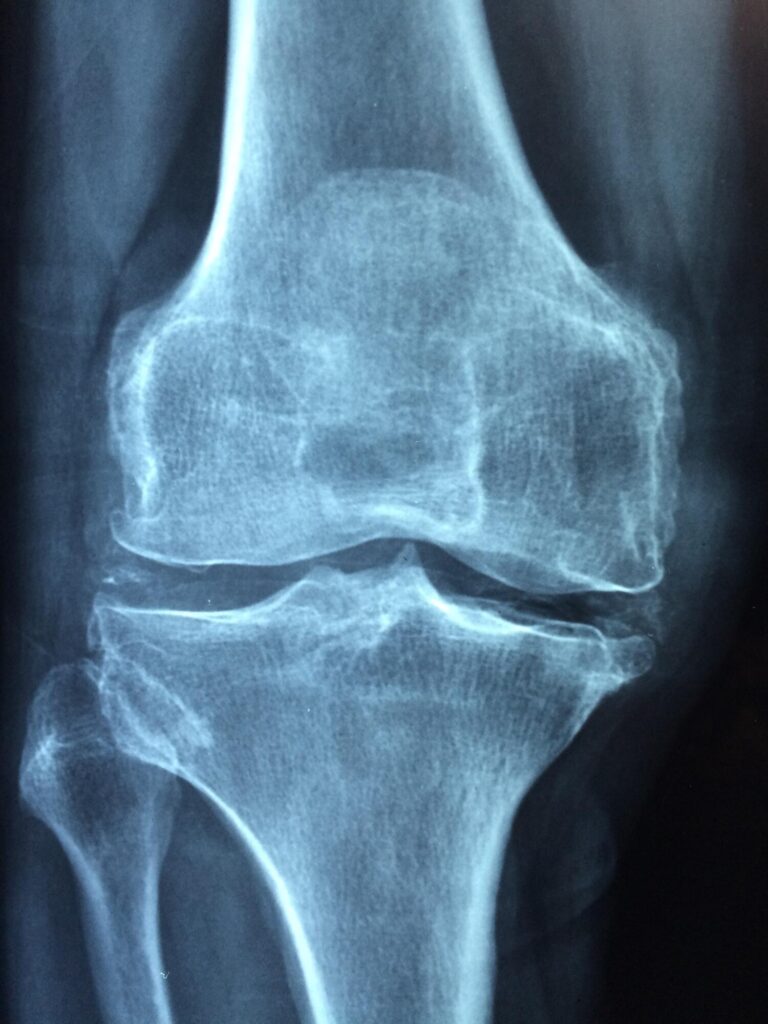

Monitoring symptoms helps prevent serious injury. Recognizing signs like swelling or limited motion, similar to common Meniscus Tear Symptoms, is essential. Early attention ensures faster recovery and better joint care.